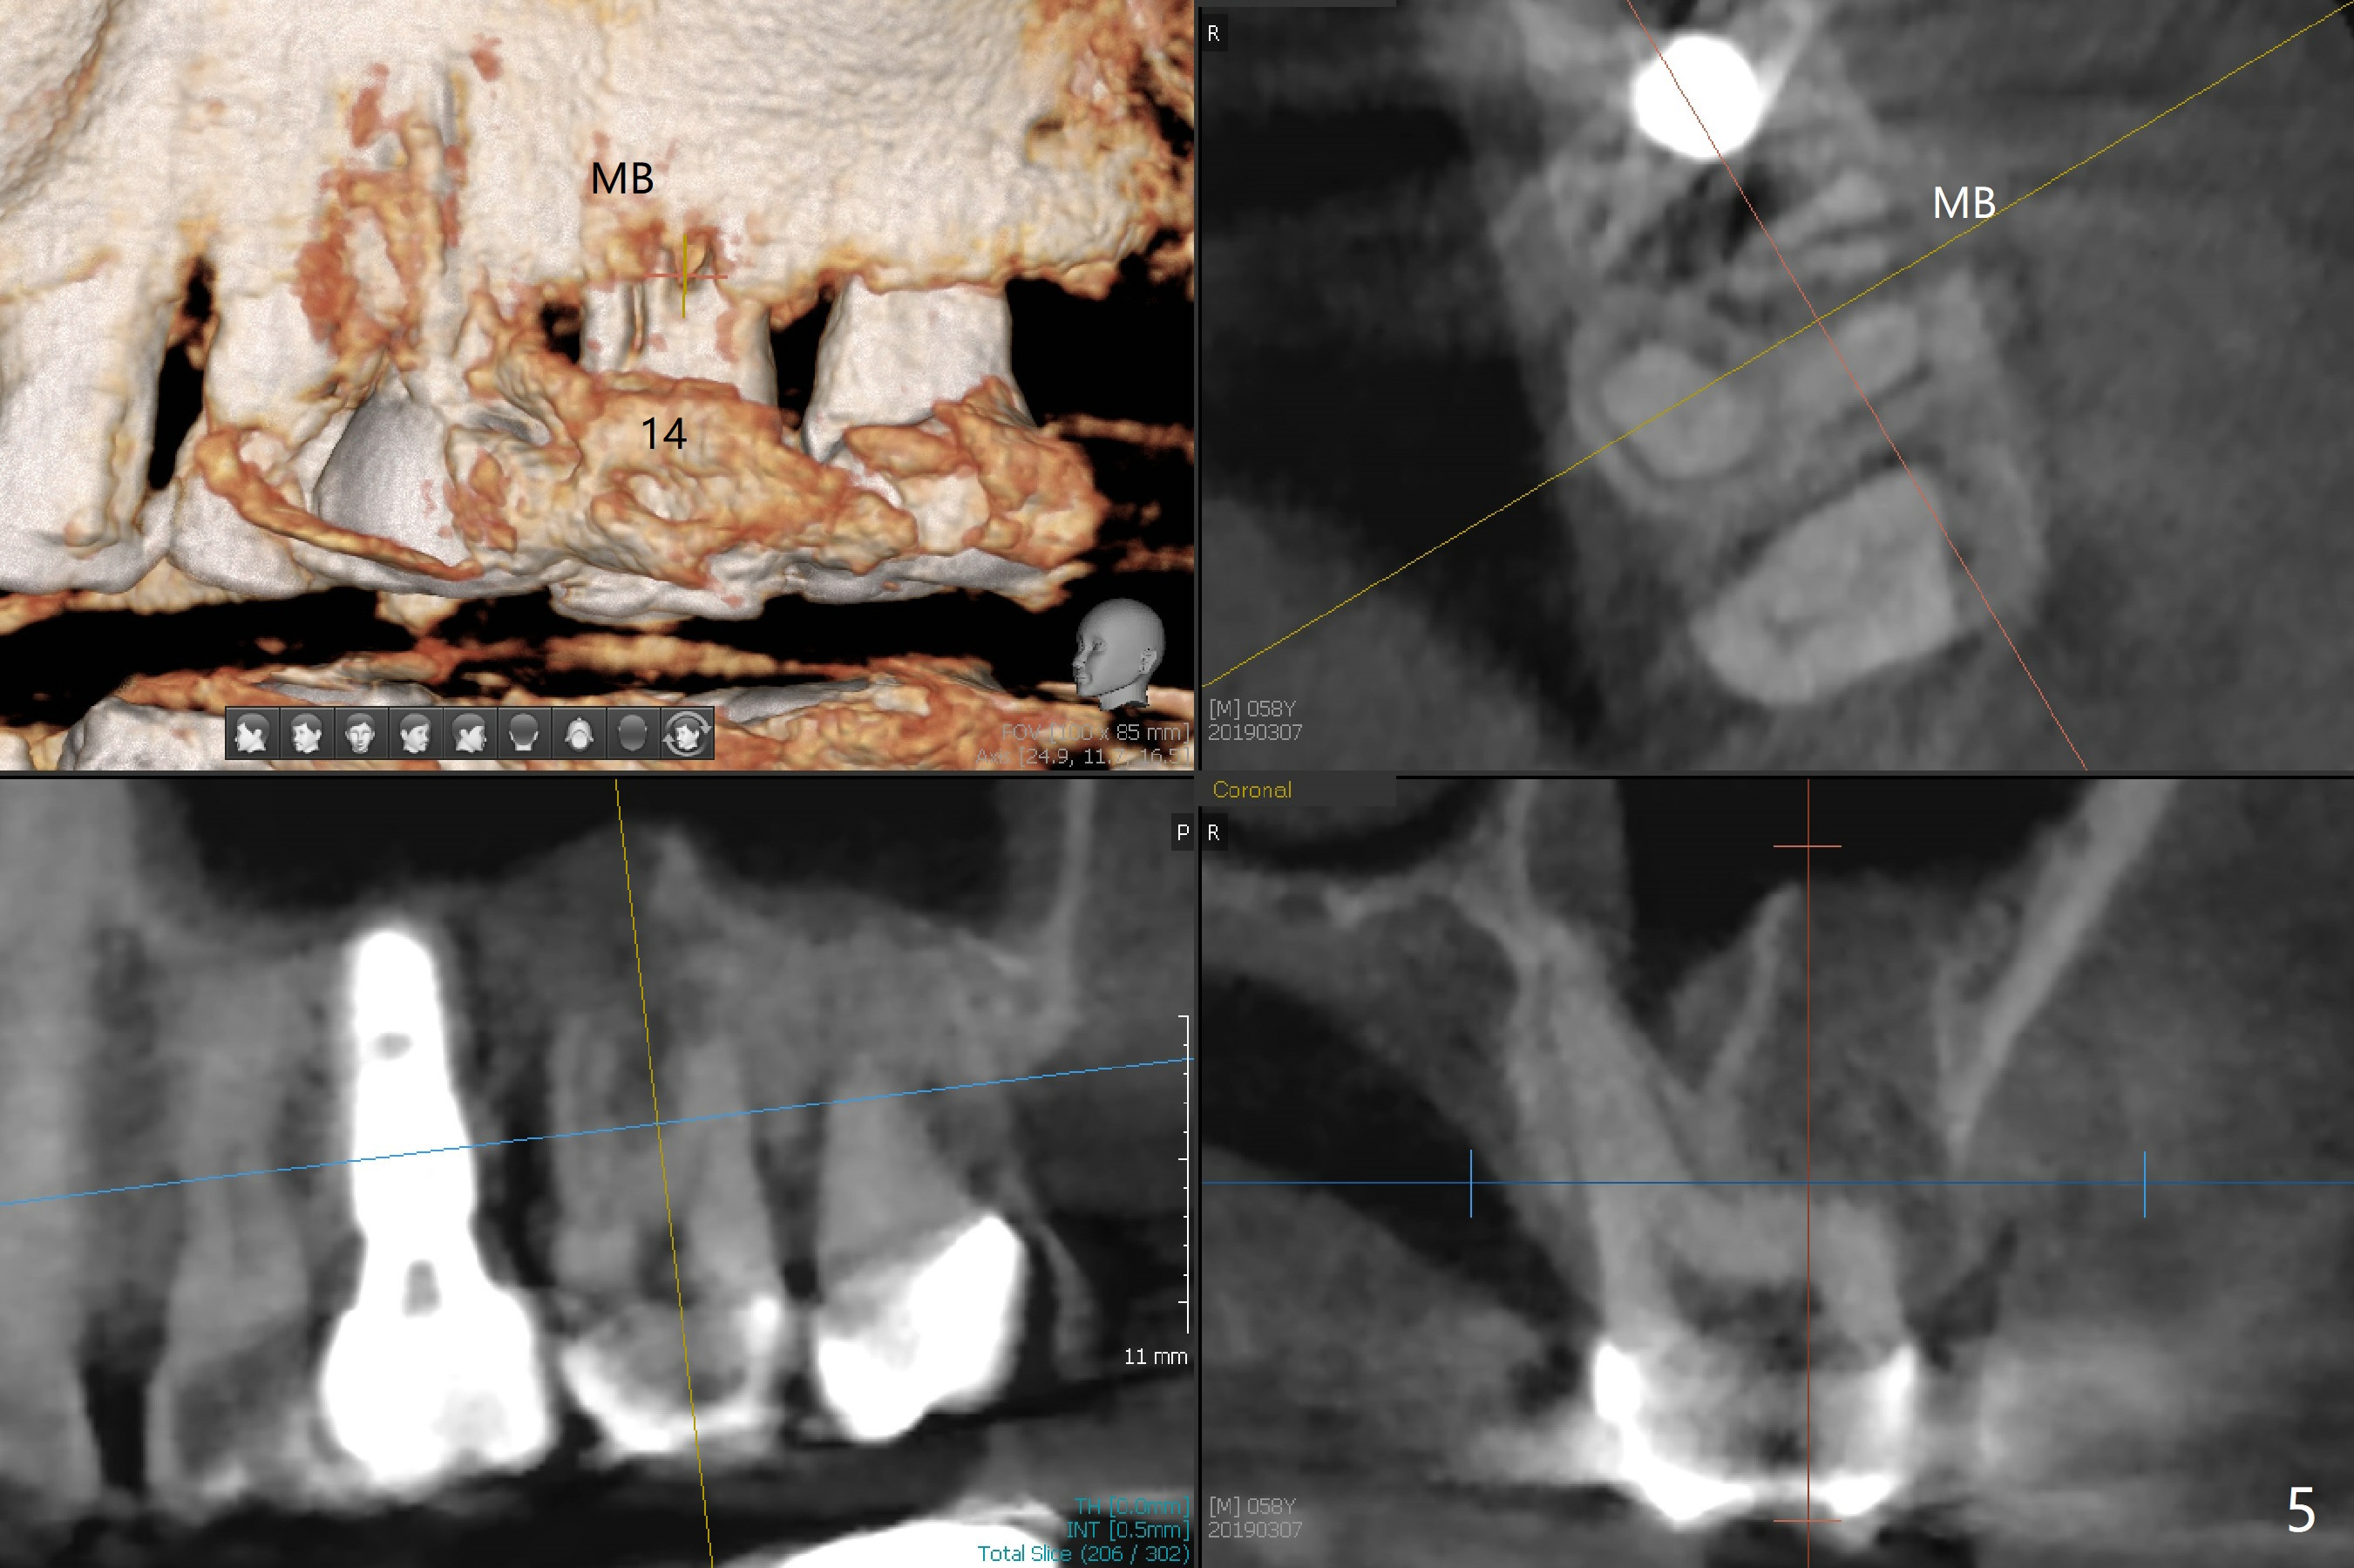

A 58-year-old man fractures the tooth #9 equigingival (Fig.1) and fiber post (Fig.2,3 *). The marginal gingiva is erythematous and edematous (Fig.1 *), suggesting biologic width violation. Redo crown would aggravate the issue. In addition, the mesiobuccal root of the tooth #14 has vertical fracture (Fig.4,5), evidence of heavy mastication. In fact the tooth #13 was also fractured apparently due to heavy occlusion before extraction. It is the best to extract the tooth #9 for implant (Fig.6), or tissue-level (3.5x14 or 17 mm).